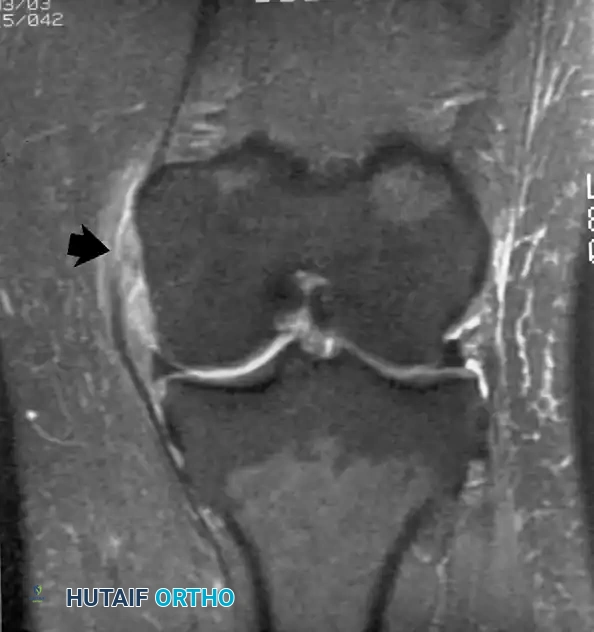

الرباط الصليبي الأمامي هو المانع الرئيسي لانزلاق عظمة القصبة للأمام. يصور الرنين المغناطيسي بدقة التمزقات الحادة في هذا الرباط، والتي غالبا ما تظهر باتجاه أفقي غير طبيعي للألياف، مع وجود كدمات عظمية مميزة في عظمة الفخذ والقصبة نتيجة اصطدامهما وقت الإصابة.

كما يستخدم الرنين المغناطيسي لتقييم الأربطة الصليبية الخلفية والأربطة الجانبية لضمان سلامتها، وهو أمر حيوي قبل التخطيط لأي جراحة معقدة.